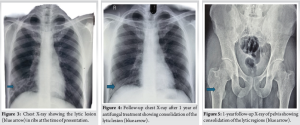

On evaluation of the swelling of the proximal thigh, X-ray of the pelvis with hip revealed a lytic lesion in the right proximal femur (Fig. 1). Further imaging with magnetic resonance imaging (MRI) revealed lytic lesions in right proximal femur and right pubic bone, with a heterogeneous hypoechoic collection in the thigh extending into the femur (Fig. 2). X-ray of the chest revealed a lytic lesion in the right 9th rib (Fig. 3). A computed tomography (CT) scan of the thorax revealed an expansile lytic lesion in 9th rib on the right side with a soft tissue collection, along with a subpleural cavitary nodule in the left lower lobe posterior basal segment. Routine sputum culture yielded no growth. Sputum acid-fast staining and culture for TB were also negative. He was hence diagnosed as a case of clinically diagnosed TB and was started on anti-tubercular therapy from elsewhere. However, even after 2 months of anti-tubercular therapy, the patient reported no improvement in symptoms and presented to our hospital.

On repeat imaging, the lesions in the proximal thigh and the chest wall were noted to have increased in size. Repeat blood investigations yielded a similar picture and repeat culture of the sputum with investigations for TB with acid-fast staining, culture, cartridge-based nucleic acid amplification test, and QuantiFERON gold TB test were negative and ruled out a tuberculous infection. We aspirated fluid from the soft tissue lesion in the right proximal femur and the right posterior chest wall for analysis, with a fine-needle aspiration cytology (FNAC) of the affected rib, cytology, extended culture for atypical organisms, and a fungal culture were sent. Although other investigations were unyielding, the fungal culture from the thigh swelling turned out to be positive for C. neoformans. A fungal culture from the collection on the chest wall and a blood culture also yielded C. neoformans. Cerebrospinal fluid (CSF) cultures were negative. Further, as Cryptococcus usually occurs in those exposed to birds, further questioning revealed exposure to pigeons at his home. Hence, he was diagnosed as a case of disseminated cryptococcosis and was started on lipophilic amphotericin B and fluconazole with serial monitoring of renal parameters. The anti-tubercular therapy was stopped. Amphotericin B was given at a dose of 0.8 mg/kg infusion over 2–4 h in 5% dextrose daily and oral fluconazole 400 mg once daily was given for 1 month. The patient became symptomatically better, and his general condition improved significantly. After 1 month of intravenous therapy, he was started on the consolidation phase with oral fluconazole 400 mg once daily for a total 8 weeks, followed by the maintenance phase with fluconazole 200 mg once daily. As cryptococcosis occurs predominantly in immunocompromised individuals, and as his HIV enzyme-linked immunosorbent assay was negative, further search into immunodeficiency was done. A clinical exome sequencing, lymphocyte subset analysis, immunoglobin profile, native T cell assay and a nitroblue tetrazolium test for immune function. The results revealed an isolated CD4 lymphocytopenia with a CD4 count of 75 (<14%) (Table 1). As he is also at risk of infection with Pneumocystis jirovecii pneumonia due to his immunodeficiency, he was also started on trimethoprim-sulfamethoxazole prophylaxis. The patient is currently at 1-year follow-up. A repeat MRI of the pelvis revealed consolidation of the lesion in the proximal femur and pubic bone. CT of the thorax revealed complete resolution of the lesions in the chest. Chest X-ray (Fig. 4) and X-ray pelvis (Fig. 5) at 1-year follow-up revealed consolidation of the lytic lesions. ESR and CRP have also stayed consistently normalized at 1-year follow-up, and the patient has been symptom free after discharge.